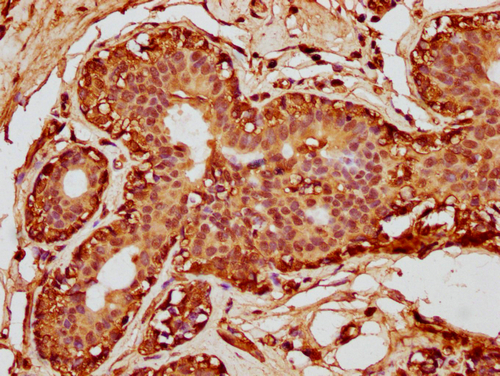

• IHC image of CSB-PA010380OA63nforHU diluted at 1:10 and staining in paraffin-embedded human breast cancer performed on a Leica BondTM system. After dewaxing and hydration, antigen retrieval was mediated by high pressure in a citrate buffer (pH 6.0). Section was blocked with 10% normal goat serum 30min at RT. Then primary antibody (1% BSA) was incubated at 4°C overnight. The primary is detected by a biotinylated secondary antibody and visualized using an HRP conjugated SP system.